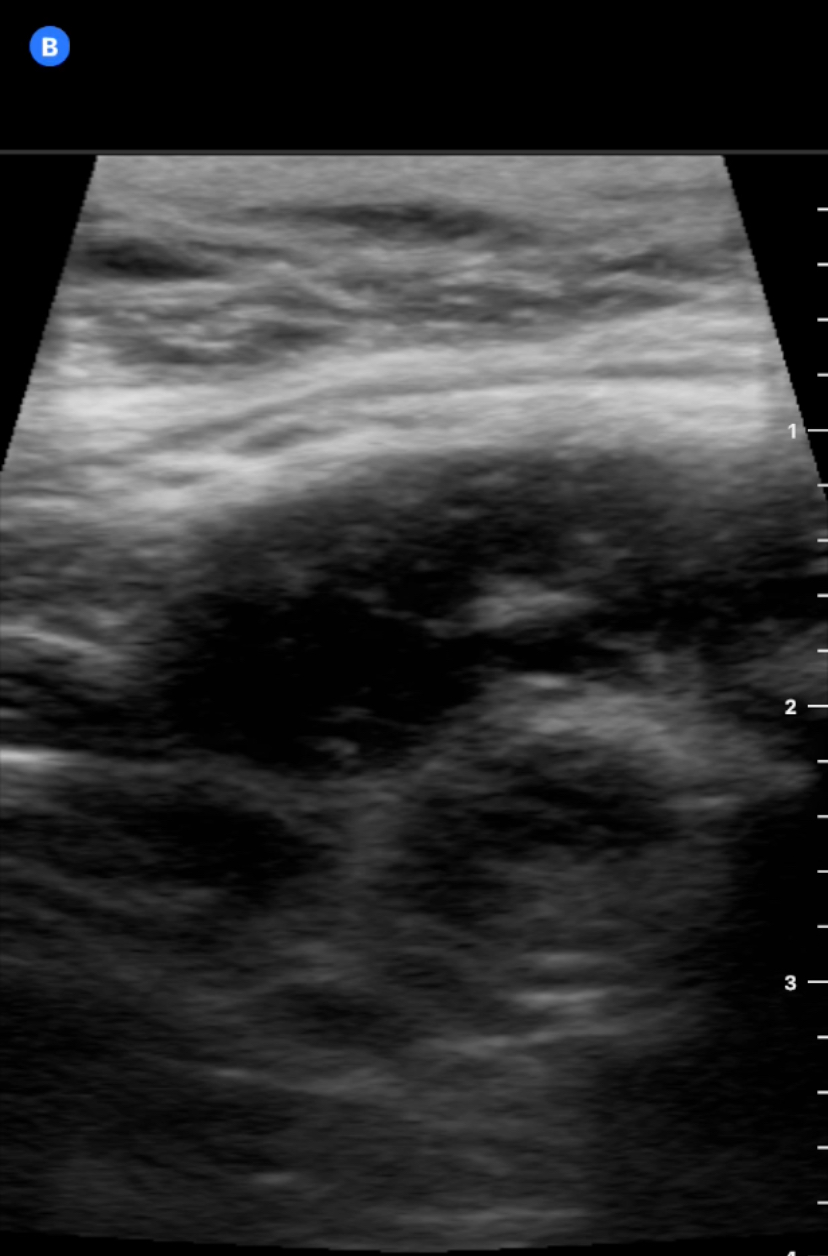

Paciente 3: con sonda lineal vemos asa intetinal engrosada (imagen de donut) y heterogenicidad alrededor del asa sugerente de abscesificación, se remite urgencias y se diagnostica de apendicitis abscesificada.